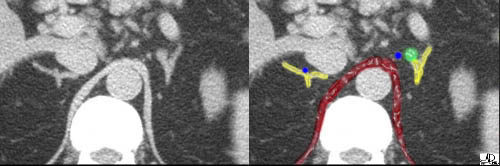

This cross sectional image shows the crus of the diaphragm (maroon), IVC (blue), and the liver (purple), surrounding the right adrenal (yellow). Courtesy of: Ashley Davidoff, M.D. |

This cross sectional image of the superior aspect of the left upper abdomen shows the spleen (dark pink), splenic artery and vein in the splenic hilum, the pancreas (light pink), crus of the diaphragm (maroon), aorta (red), and the spine surounding the left adrenal (yellow). Courtesy of: Ashley Davidoff, M.D. |